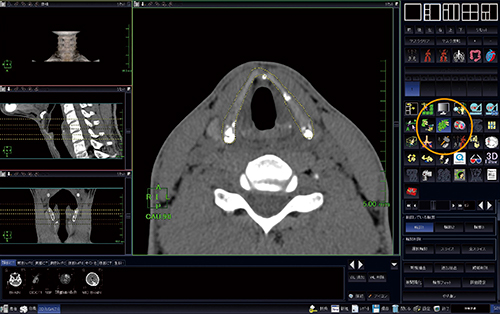

軟骨部分を分離して評価を行うために,AZE VirtualPlace 新NTのセミオート抽出機能を使用してVR画像を作成した(図3)。数枚のスライス上で手動にて輪郭を設定するが,スライスの間の輪郭はソフトウェアが自動的に補間するので,連続したボリュームのマスクとなる。ソフトウェアの自動補間機能の精度は高く,本症例では,約4cmの甲状軟骨で0.625mm厚,70スライス程度のデータだったが,5,6スライスの輪郭をトレースしただけで自動補間し,マスク化することが可能であった。

図3 セミオート抽出機能

セミオート抽出機能(○)を使用し,ボリュームで抽出したい部分の輪郭を,何枚かのスライス上で設定する。各スライス上での輪郭設定後,抽出ボタンでマスク化を行う。